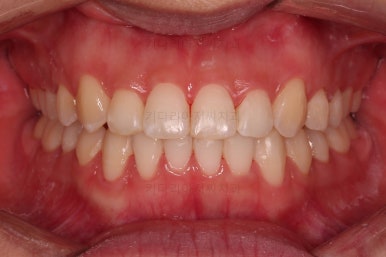

치료가 1년만에 종료가 되었네요.

치아가 가지런해졌고, 교합이 잘 맞는 모습이에요.

부산교정 전후사진을 비교해 볼게요.

치열의 모습이 좋아졌고, 웃을 때 보이는 치열이 가지런해서 미소도 훨씬 예뻐졌네요.

옆라인이라던지 입을 다물었을 때의 느낌은 원래도 좋으셨기 때문에 거의 그대로 유지가 되었고요.

1년정도 만의 만족스러운 치료였습니다.